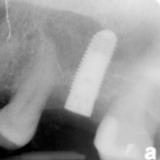

Immediate Implant Placement

A molar either maxillary or mandible always represents a little difficult and tricky scenario for implant placement immediately after extarction. There is always some sacrifice for the location, angle etc. however you save some time and patients go through a procedure once and it is a reliable method of replacing a tooth, when feasible. Dental implant is always a compromised replacement and a tooth restored with immediate placement is not any different.